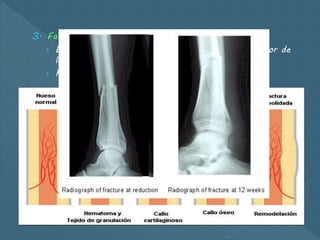

 Formación del callo

1. Fase inflamatoria.

› Hematoma que se coagula

› A las 18-20 horas la capa más profunda del periostio

comienza a proliferar.

2. Fase reparativa.

› Inicia con reorganización del coágulo

› Osteoblastos rodean cada fragmento, crecen hacia el otro

fragmento, así como del endostio y médula ósea.

› Osteoblastos producen osteiode y se deposita sobre el

hueso adyacente.

3. Fase de remodelación

› El hueso nuevo forma un collar redondeado alrededor de

la fractura

› Remodelación ósea  callo maduro

 Formación delcallo 1. Fase inflamatoria. › Hematoma que se coagula › A las 18-20 horas la capa más profunda del periostio comienza a proliferar. 2. Fase reparativa. › Inicia con reorganización del coágulo › Osteoblastos rodean cada fragmento, crecen hacia el otro fragmento, así como del endostio y médula ósea. › Osteoblastos producen osteiode y se deposita sobre el hueso adyacente.

3. Fase deremodelación › El hueso nuevo forma un collar redondeado alrededor de la fractura › Remodelación ósea  callo maduro